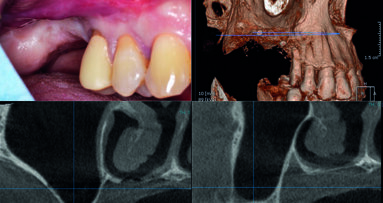

L’atrofia del mascellare posteriore come conseguenza della perdita degli elementi dentali è una condizione piuttosto frequente nella pratica clinica. La ...